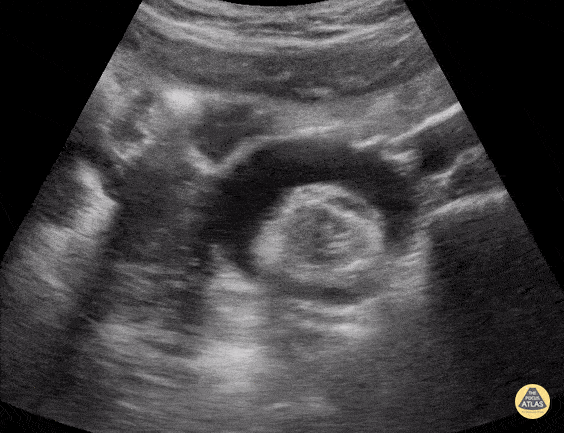

Renal & Bladder Pathology

Peds-Genitourinary